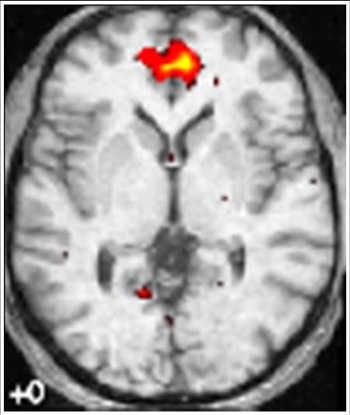

Scientists have discovered what happens in the brain when the mind wanders. Until recently, little has been known about the neural mechanisms that give the mind its ability to daydream.

But now psychologists and neuroscientists in Aberdeen and America have revealed that a collection of areas in the brain termed the default network, supports what is known as mind wandering.

The results revealed that when participants performed practised tasks with which they were familiar, activity in regions of the default network was associated with episodes of mind wandering, a finding that underscores the importance of this system in guiding the stream of consciousness.